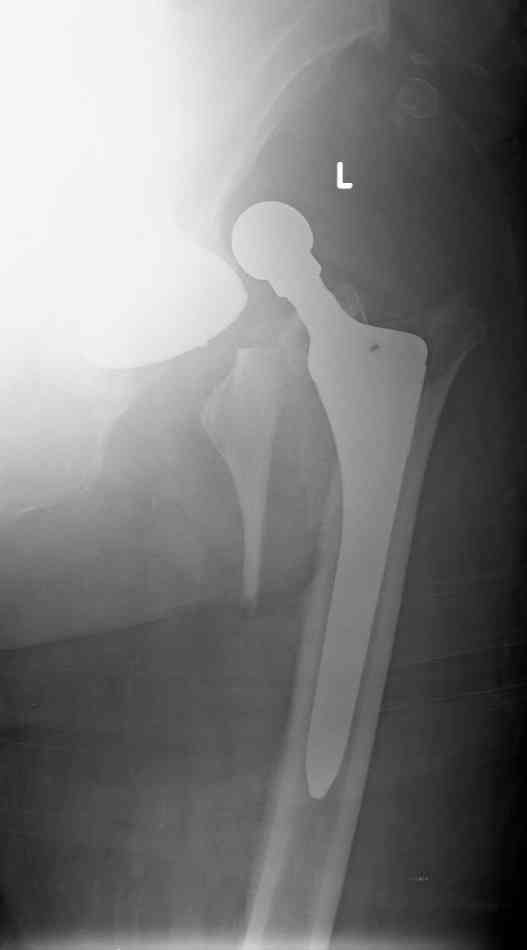

Patient 77 yaers old man falled two day after elective THR operation.

Was done noncemented THR,

Direct Lateral Approuch .

During posedure wasn't any complication.

Now we have Vancouver AL fracture (to be more prosize between A to B1).What your sudgests?